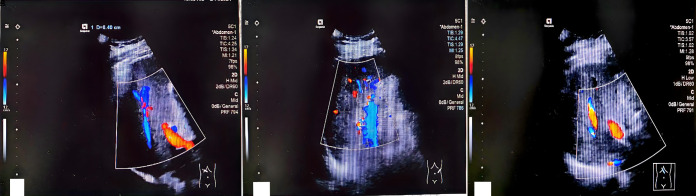

Glucagon-like peptide-1 (GLP-1) and glucose-dependent insulinotropic polypeptide (GIP) receptor agonists are increasingly used in the management of type 2 diabetes mellitus and obesity due to their ability to stimulate insulin secretion, delay gastric emptying, and suppress appetite. The combination of GLP-1 and GIP agonists improves glycemic control and promotes weight loss. However, the introduction of these novel therapies has raised safety concerns, including the risk of cholestatic hepatitis. We report a case of a patient with obesity who was prescribed a GLP-1/GIP dual-receptor agonist as part of his treatment regimen. Importantly, both before the initiation of this therapy and during the course of treatment, the patient was not taking any other medications. Shortly after receiving four doses of the therapy, the patient developed symptoms of severe cholestatic hepatitis, including jaundice and elevated liver enzyme levels. During hospitalization, no alternative causes for the condition were identified, and a liver biopsy confirmed the diagnosis of drug-induced cholestatic hepatitis. This is the first recorded case of cholestatic hepatitis induced by a GLP-1/GIP dual agonist, and it aimed to raise global awareness of this potential side effect.

Abstract Image